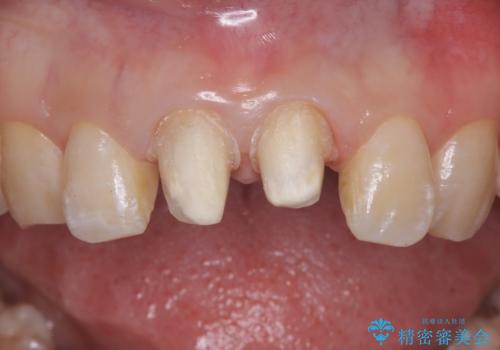

- 前歯の違和感を主訴にご来院された患者様です。

根尖性歯周炎に罹患し根の先に膿が溜まっているのが原因でした。

精密根管治療後、オールセラミッククラウンで治療を行いました。

精密根管治療では、菌を入れない環境を作り見逃しが無いようにマイクロスコープを使って治療する事が大切です。

まだ誰も触っていない根管ならばほとんどのケースで治せる事が出来ます。